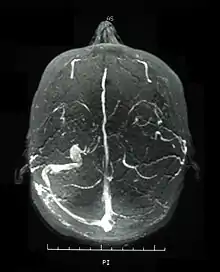

Magnetic resonance venogram demonstrating occlusion of the left sigmoid and transverse sinuses